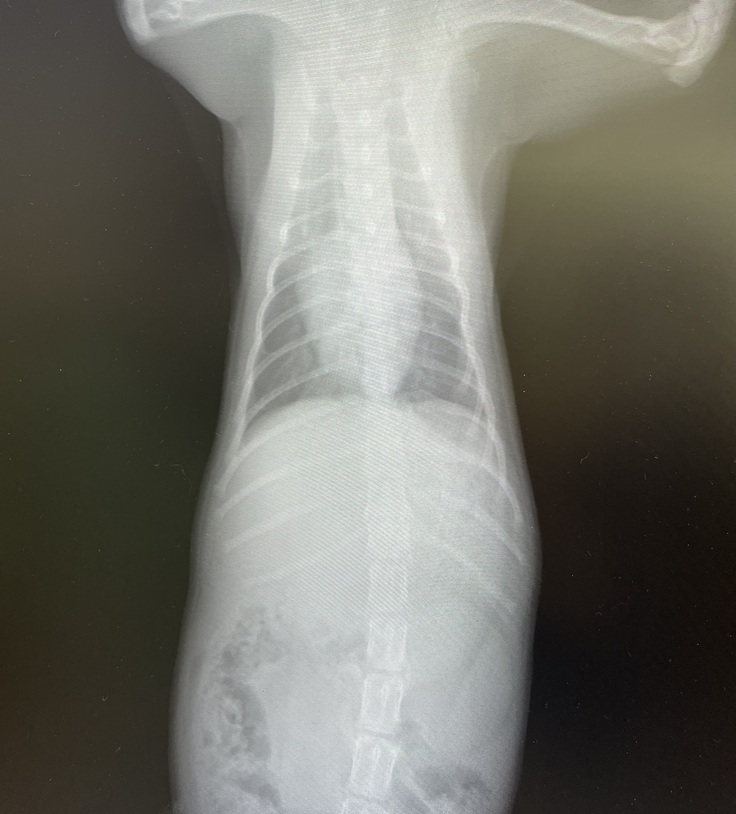

まずはレントゲンを撮ってもらいました。

エルちゃんのお腹の中、以前と比べるととっても綺麗になっていました😭

先生も、「もう問題ないし、大丈夫だね!エルちゃん本当に本当によく頑張ったね。お母さんが大事にお世話してくれたおかげだね。」と言ってくださいました。

レントゲン撮る時も、注射打つ時もお利口さんにしてて、エルちゃんとってもいい子でした☺️